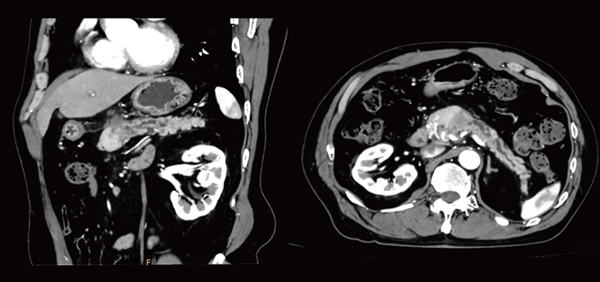

[CT 5300の臨床画像]

高画質CTA画像(Precise Image)

高画質膵臓がん症例

(Precise Image,2mmスライス画像)

「Precise Imageによって以前よりもノイズが大幅に低減し,コントラストが向上しているため,3D画像の作成においては,ワークステーションによる骨や血管の自動抽出の精度が向上しました。末梢血管は通常,ノイズに埋もれてコントラストも付きにくく,3D画像の作成が非常に難しいのですが,現在は作成の手間が以前の半分以下になり,ストレスも軽減しています。また,頸部の撮影では肩のアーチファクトが劇的に低減し,鎖骨下動脈や肩周りの画像再構成が簡単に行えるようになりました」

さらに,同センターでは,和歌山県立医科大学から膵臓のthin slice画像の撮影依頼を受けることが多いが,Precise Imageによってノイズが以前よりも大幅に低減し,微小病変も明瞭に描出されるなど,診療に大きく寄与する画像を提供できるようになった。肝臓のCTも,Precise Imageによってコントラストが向上した結果,造影剤量を約20%低減しても,以前と同等の画像が得られている。肝臓以外の造影検査でも同様の効果が得られており,患者の負担軽減に貢献している。